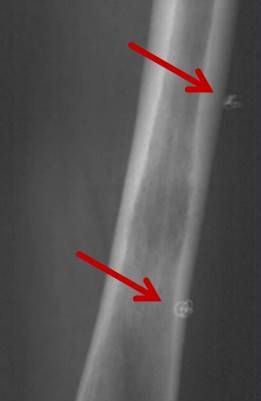

Abbildung: Osteoidosteom (Pfeil) im Schienbein bei einem jungen Patienten. Unter CT-Bildgebung wird ein spezieller Applikatoren unter CT-Bildgebung in das Osteoidosteom eingebracht. Durch Hitze wird dieses effektiv und dauerhaft zerstört.